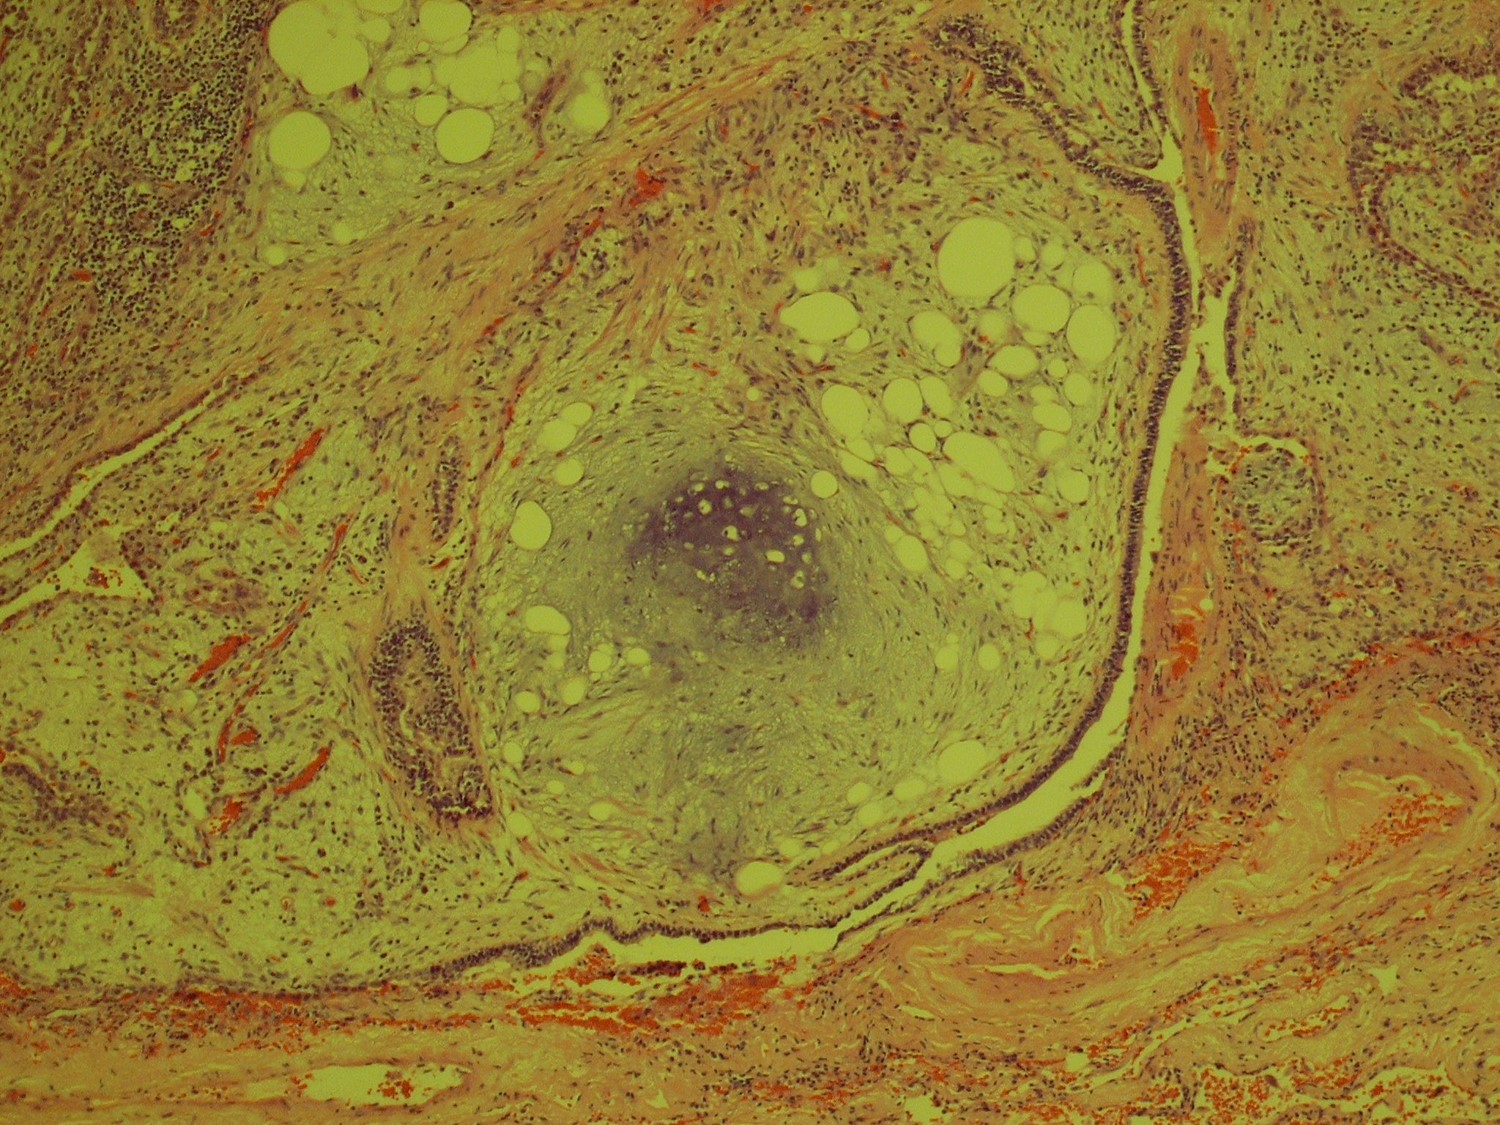

| The answer is “C”, Fibrotic NSIP with DIP- like reaction For most patients who undergo VATS biopsies for interstitial lung disease, the fundamental question is, “Is this IPF?” For the pathologist, that translates to “Is this UIP or could it be something else?” This case lacks the geographic and temporal heterogeneity of interstitial fibrosis characteristic of UIP. There is no honeycomb change and there are no fibroblastic foci. It is not UIP/IPF. Instead, there is uniform, bland fibrous thickening of alveolar septa in specimens from all three lobes, characteristic of fibrotic non-specific interstitial pneumonitis (NSIP). The abundant intra-alveolar pigmented macrophages raise the possible diagnosis of desquamative interstitial pneumonitis (DIP), a condition highly related to smoking. In fact, cases of DIP can have areas of NSIP-like interstitial fibrosis, but these are usually focal and more scar like. In cases in which the septal fibrosis is uniform and widespread, the diagnosis of NSIP with DIP-like reaction is preferred. The final two images are a bonus, an incidentally discovered pulmonary hamartoma from the right lower lobe wedge biopsy. Katzenstein, AL, Katzenstein and Askin’s Surgical Pathology of Non-Neoplastic Lung Disease, Major Problems in Pathology (MPP 13), Fourth Edition. Saunders, 2006. Pp. 61-74. |